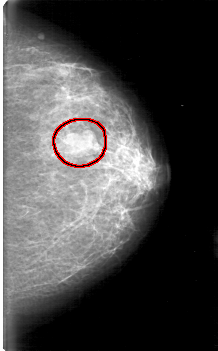

D_4075_1.LEFT_MLO

LEFT_MLO LINES 5251 PIXELS_PER_LINE 3136 BITS_PER_PIXEL 12 RESOLUTION 43.5 OVERLAY

FILE: D_4075_1.LEFT_MLO.OVERLAY

TOTAL_ABNORMALITIES 1

ABNORMALITY 1

LESION_TYPE MASS SHAPE LOBULATED MARGINS CIRCUMSCRIBED

ASSESSMENT 0

SUBTLETY 5

PATHOLOGY BENIGN

TOTAL_OUTLINES 1

BOUNDARY